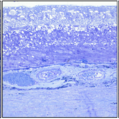

Best Vitelliform Macular Dystrophy

Best Vitelliform Macular Dystrophy

Dec 10 2020 by McGill University Health Centre

Postmortem eyes from 101-year-old female. Past clinical history includes a poor vision for many years due to macular degeneration. The last visual acuity test recorded 6/15 OD and 6/6 OS. IOP 14 and 18 torr OS. Histopathology: Disclosed and yellow 2x2mm macular lesion. Microscopic examination: elevated placoid macular lesion with overlying pigment granules. Electron microscopy examination: pigment granules with abundant lipofuscin and melanolysosomes, photoreceptor cells markedly attenuated (less degenerated at the periphery) Numerous calcified drusen throughout the retina particularly in the posterior pole. RPE lipofuscin content is elevated in Best’s dystrophy. The extractability of the PRE lipofuscin fluorophores is reduced (it is normal during senescence). The defect in Best’s dystrophy accelerates this age related change in lipofuscin.

Condition/keywords: Best vitelliform macular dystrophy (BVMD), histopathology, pathology